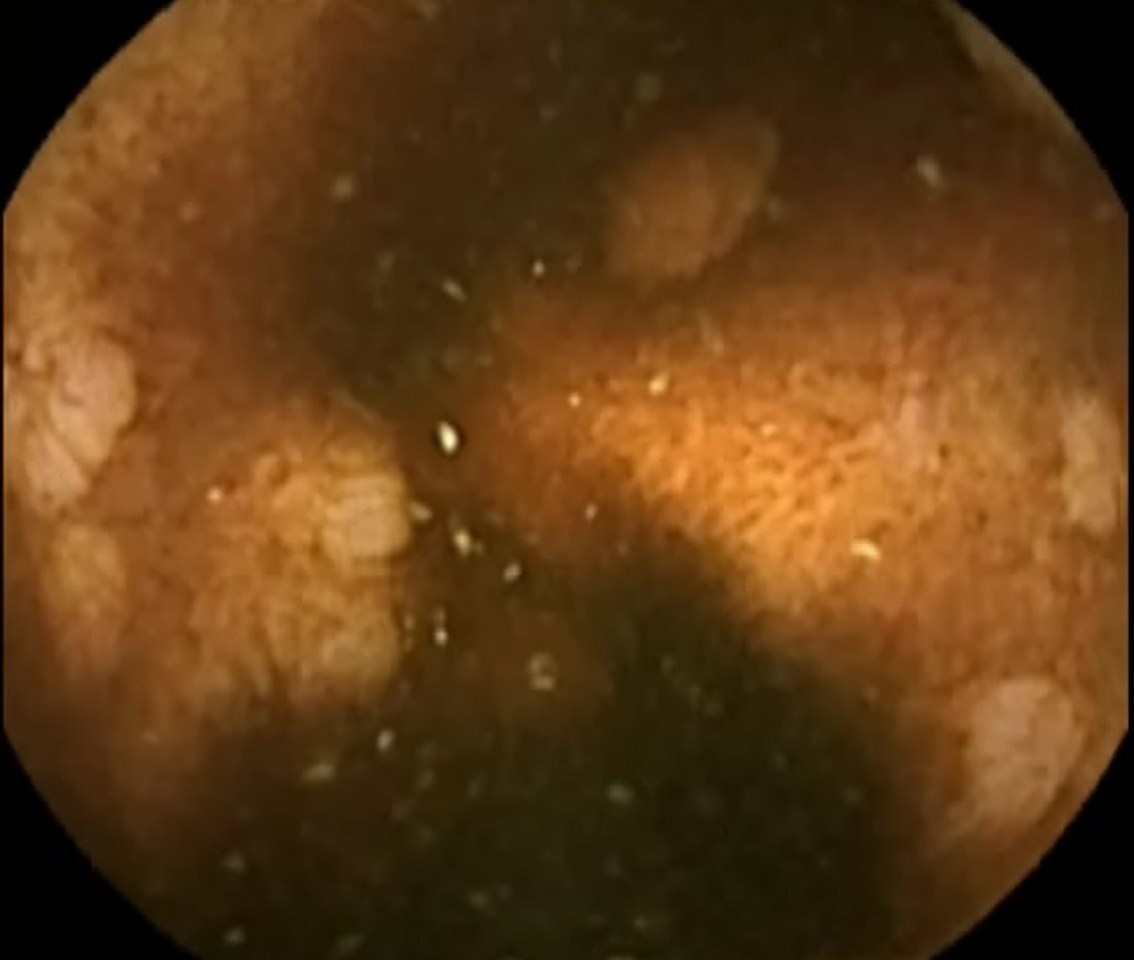

Capsule Endoscopy: Ileum Terminale, Lymphoid Hyperplasia

Capsule Endoscopy: Ileum Terminale, Lymphoid Hyperplasia. Just click on a picture!